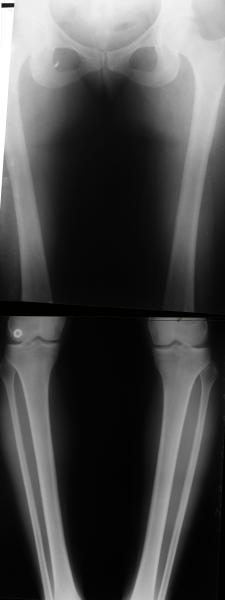

Вот ещё картинки, которые отправлял в Ортопод. Коррекция кривизны и удлинение на 3 см.

Снимки в приложении - фас сравнительный с неоперированной ногой. Жду критики.

Впрос про остеотомию большеберцовой непраздный. Эта получилась при надломе несколько более наклонно, чем я делал (сейчас проблема,

как на второй ноге сделать так же). Вот этот высоящий "зуб" центрального отломка не заменит ли в плане косметики то, что получается при медиализации дистального?

The analysis in the attached images is direct, just using the tools.

Tibial tilt is perhaps more than you want but the tibial correction is to 90 (very slight over

correction.

Will need full length views to tell us about the hka but it appears neutral.